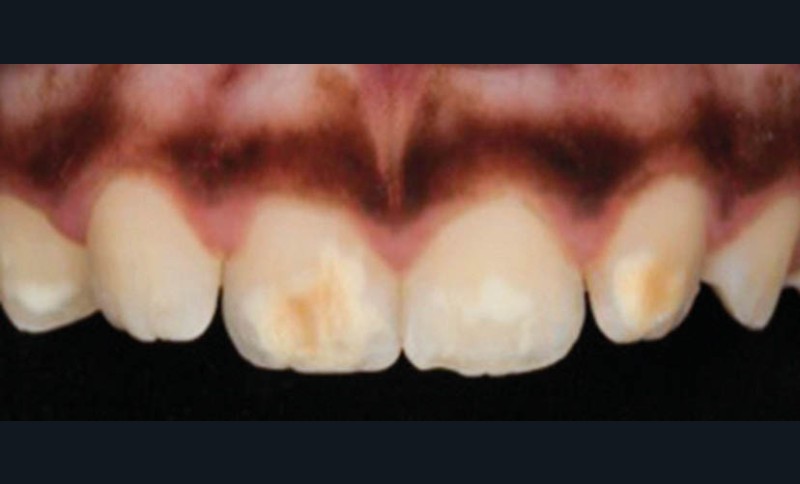

L’émail dentaire, tissu le plus dur et le plus minéralisé du corps humain, peut être affecté par des anomalies génétiques inscrites dans le génome de l’individu, mais également par des facteurs environnementaux. Ces facteurs sont multiples et signent un événement ou une exposition à un xénobiotique au cours de la vie de l’individu. Parmi les atteintes développementales acquises de l’émail, outre la fluorose, figurent les hypominéralisations à type de MIH (Molar Incisor Hypomineralization). Celles-ci sont observées de manière caractéristique sur une ou plusieurs premières molaires permanentes et potentiellement les incisives permanentes éruptant vers l’âge de 6 à 7 ans d’après la description qui en a été faite en 2001 [3] (fig. 1 à 3). La prévalence est importante, la MIH touchant, selon les méta-analyses les plus récentes, plus de 13 % des individus dans le monde, et peut varier selon les études et les pays dans lesquels elles sont menées [4, 5]. Son étiologie est encore incertaine, mais la communauté scientifique s’accorde sur le fait qu’elle serait multifactorielle et notamment en lien avec la survenue d’une hypoxie à la naissance, de fortes fièvres, des épisodes infectieux de la sphère ORL dans la petite enfance ou encore avec une prédisposition génétique [6]. Cette pathologie aurait toujours existé, mais sa prévalence semble être en nette augmentation. Peu d’études ont été réalisées sur cette évolution dans le temps [7].

Les cellules responsables de la synthèse de l’émail, les améloblastes, disparaissant au moment de l’éruption des dents, les défauts de structure et de qualité de l’émail sont irréversibles. L’émail dentaire est ainsi capable d’enregistrer des événements environnementaux ayant eu lieu lors de sa formation. Ces défauts sont donc en quelque sorte le disque dur des contaminations que les améloblastes ont subies. De ce fait, le défaut de minéralisation caractérisant le MIH est le signe d’une exposition environnementale délétère intervenue au cours de la période périnatale (période d’amélogenèse des dents impactées par le MIH), soit environ 5 ans avant leur éruption (fig. 4).

Les leviers à activer dès maintenant pour répondre aux enjeux de santé publique liés à la MIH sont nombreux. C’est d’abord le développement de la collaboration avec les professionnels de santé de la petite enfance. Ceux-ci, dont les médecins généralistes, doivent être sensibilisés au tableau clinique de la MIH – différent de celui de la fluorose ou de l’amélogenèse imparfaite par son caractère asymétrique et sa localisation préférentielle aux molaires et incisives permanentes – afin de favoriser son dépistage et sa prise en charge précoce.